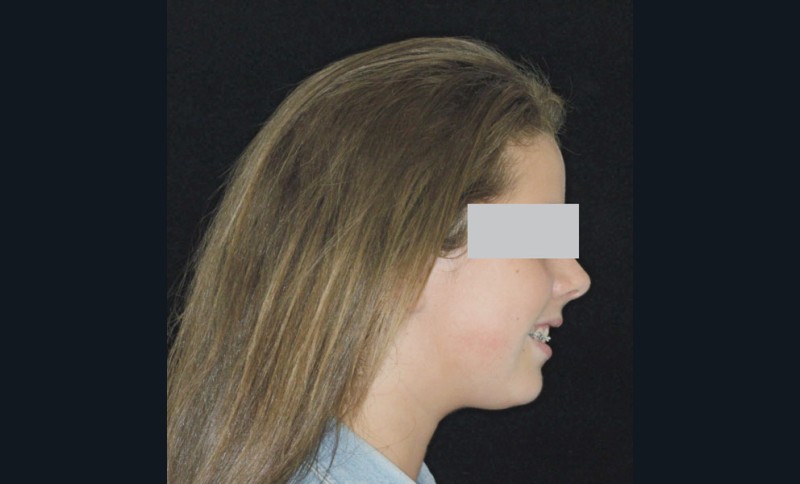

Camille âgée de 12 ans et 7 mois se présente à la consultation adressée par son chirurgien-dentiste.

Son profil convexe s’inscrit dans un contexte de rétrognathie hyperdivergente associée à une proalvéolie et un encombrement maxillo-mandibulaire.